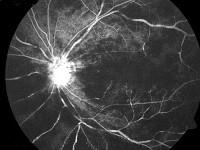

问题 患者,男性,60岁,高血压病史10年,近1周突感左眼视力下降,视力由原来的0.8降至0.04,裂隙灯检查见眼前段(-),眼底检查如图,符合该病的描述的是 ( )

选项 A、该病可分为缺血型和非缺血型两种 B、该病应寻找病因,积极治疗原发病 C、该病好发于颞下支 D、动静脉交叉处、动脉壁增厚对静脉的压迫为最常见原因 E、黄斑水肿是引起该病视力下降的主要原因

答案 ABDE